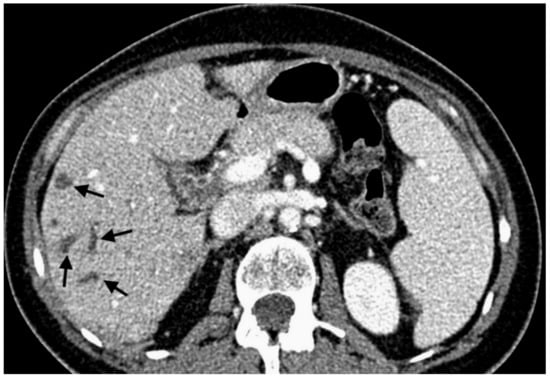

With 192 chemoembolizations, 14 (7.3%) serious complications were found. The most complications were found with the administration of embolizate at the level of the lobar arteries. There was no significant correlation between the branch level of embolization and the presence of complications (chi-squared = 2.9331, df = 2, p-value = 0.2307; Table 5). In two cases, an anaphylactic reaction occurred with moderate hypotension, skin redness, and coughing occurring during the procedure; this resolved after the intervention of the anesthetic team. Two other patients with severe and prolonged pain in the right upper quadrant showed signs of cholecystitis (without bilirubin increase) in ultrasound, which resolved after conservative treatment. In another two patients, features of liver decompensation with ascites were found. One patient experienced a septic episode with liver abscess 2 weeks after the last treatment, which was successfully treated by antibiotic therapy. Follow-up imaging studies showed signs of dilatation of the bile ducts in two patients as a result of damage, (Figure 1). Two patients had occlusion of the right or left branch of the hepatic artery (Figure 2). Three patients, 21 days after surgery, had leukopenia <2000 mm3, requiring the date of the next transcatheter arterial chemoembolization (TACE) session to be shifted by an additional week or two. There were no deaths in the periprocedural period or within 30 days of the procedure.

Figure 1. Contrast-enhanced multidetector computed tomography scan showing bile duct dilatation (black arrows) after transarterial chemoembolization with drug-eluting microspheres preloaded with irinotecan.